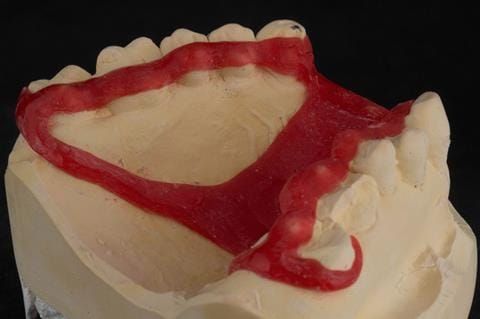

- Extract the upper 2-2 teeth and replace with an interim acrylic based partial denture. Reline the interim denture over 9 - 12 months, replacing with a definitive cobalt chromium based partial denture. The definitive denture would ideally be designed as an occlusal protective splint to reduce the the potential for mechanical wear and breakages of the moderately/heavily restored maxillary dentition. In addition, should further upper teeth require extraction they could be added on to the denture cobalt chromium framework - therefore a new prosthesis would not be required as future teeth are lost. This option would produce an excellent aesthetic outcome. This is the option the patient chose to have.

Following consultation and second discussion appointment the patient chose to have option 3 namely, a maxillary cobalt chromium based partial denture/protective occlusal splint. The clinical situation and treatment process is shown in detail below with photographs. The patient was successfully rehabilitated with this and her quality of life considerably improved. The clinical work was provided by Finlay and the technical work by Rowan.